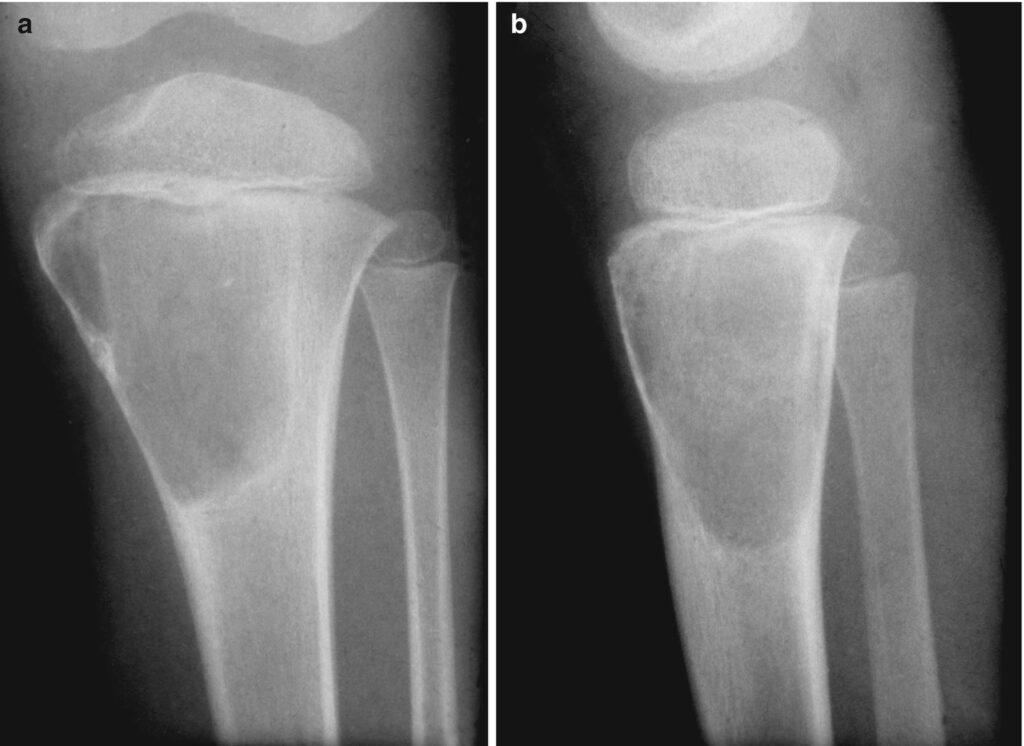

Esiste una categoria di anomalie ossee che da occhi non esperti potrebbero essere scambiate per delle cisti. Stiamo parlando dei fibromi non ossificanti. Molto diffusi, colpiscono infatti un bambino su cinque, non sono in realtà pericolosi in quanto vengono considerati “normali errori” dello sviluppo corticale. Sono asintomatici e spesso vengono scoperti casualmente e di rado portano a fratture patologiche. In questi casi il tessuto osseo è sostituito dal tessuto fibroso durante la fase dello sviluppo scheletrico. Non essendo pericolosi, l’unico accorgimento per il medico è quello di monitorarli nel tempo con controlli a cadenza annuale. La rimozione chirurgica si rende necessaria qualora le dimensioni siano eccessive (più del 50% del diametro dell’osso nel quale si formano).